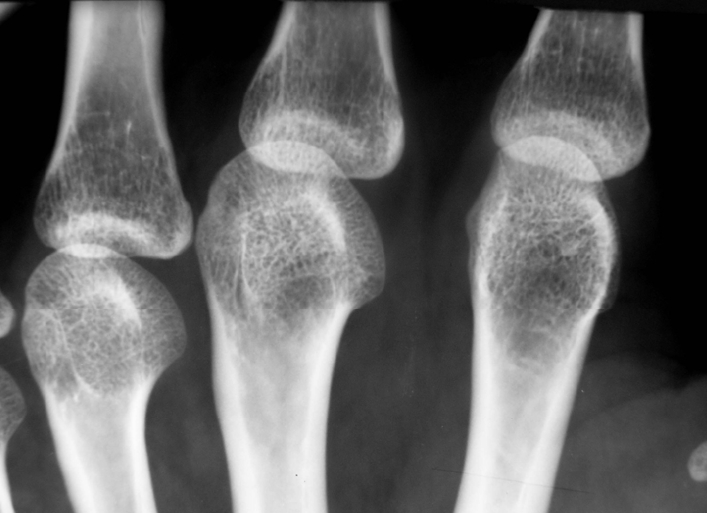

На рентгеновских снимках можно заметить первые признаки заболевания, что служит основанием для проведения более тщательного обследования.

Проблемы с костной тканью четко видны на рентгеновских снимках. Первым признаком являются просветления, указывающие на снижение плотности и деминерализацию. На изображениях заметны изменения формы позвонков, которые становятся вогнутыми или клиновидными из-за сплющивания и уменьшения высоты. Этот симптом называется «рыбные позвонки». В патологический процесс вовлечены не только отдельные позвонки, но и несколько сегментов позвоночного столба.

На рентгеновском снимке видны большие участки просветления, из-за которых кость выглядит полупрозрачной. Наблюдаются утолщенные трабекулы, а позвоночный канал расширяется.